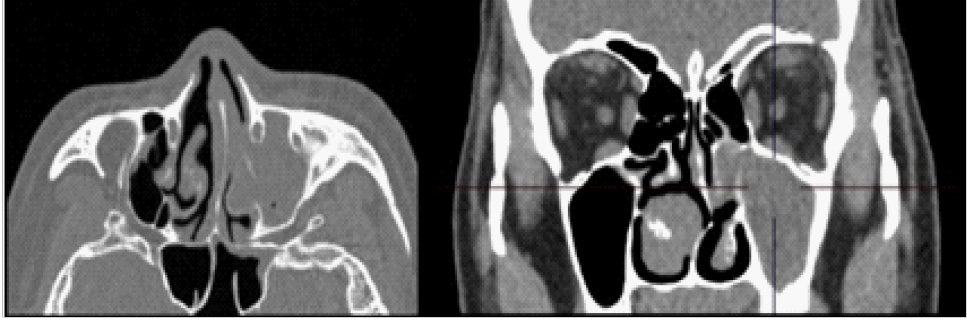

В заднем сегменте глазного яблока отмечалась дополнительная структура диаметром 8,5 мм, плотность 92 HU. В области сканирования левая верхнечелюстная пазуха тотально заполнена содержимым, ячейки решетчатой кости с субтотальным заполнением просвета (рис. 5).

Рис. 5. Компьютерная томограмма области околоносовых пазух

С учетом состояния верхнечелюстной пазухи и ячеек решетчатой кости пациент был направлен на консультацию к оториноларингологу, который выполнил лечебно-диагностическую пункцию левой верхнечелюстной пазухи, при которой получено слизистое отделяемое в объеме 2 мл. В лабораторных исследованиях отмечался лейкоцитоз (12,067 х 10^9/л), остальные показатели клинического анализа крови, а также СОЭ, С-реактивный белок, фибриноген, ревматоидный фактор соответствовали норме.